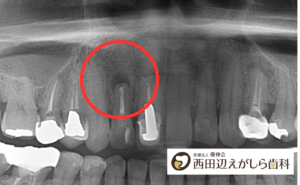

レントゲン検査で分かること

根尖性歯周炎は、見た目だけで診断することはできません。

そのため、レントゲン検査が非常に重要になります。

レントゲン写真では、歯の根の先に黒い影が見えることがあります。これは、炎症によって骨が吸収されている状態を示しています。

当院では、必要に応じて歯科用CTを使用し、根の形や炎症の広がりを立体的に確認します。これにより、より正確な診断と治療方針の判断が可能になります。

歯性上顎洞炎との関係

上の奥歯の根は、鼻の横にある「上顎洞(じょうがくどう)」と非常に近い位置にあります。

そのため、根尖性歯周炎が進行すると、炎症が上顎洞に広がり、歯性上顎洞炎を引き起こすことがあります。